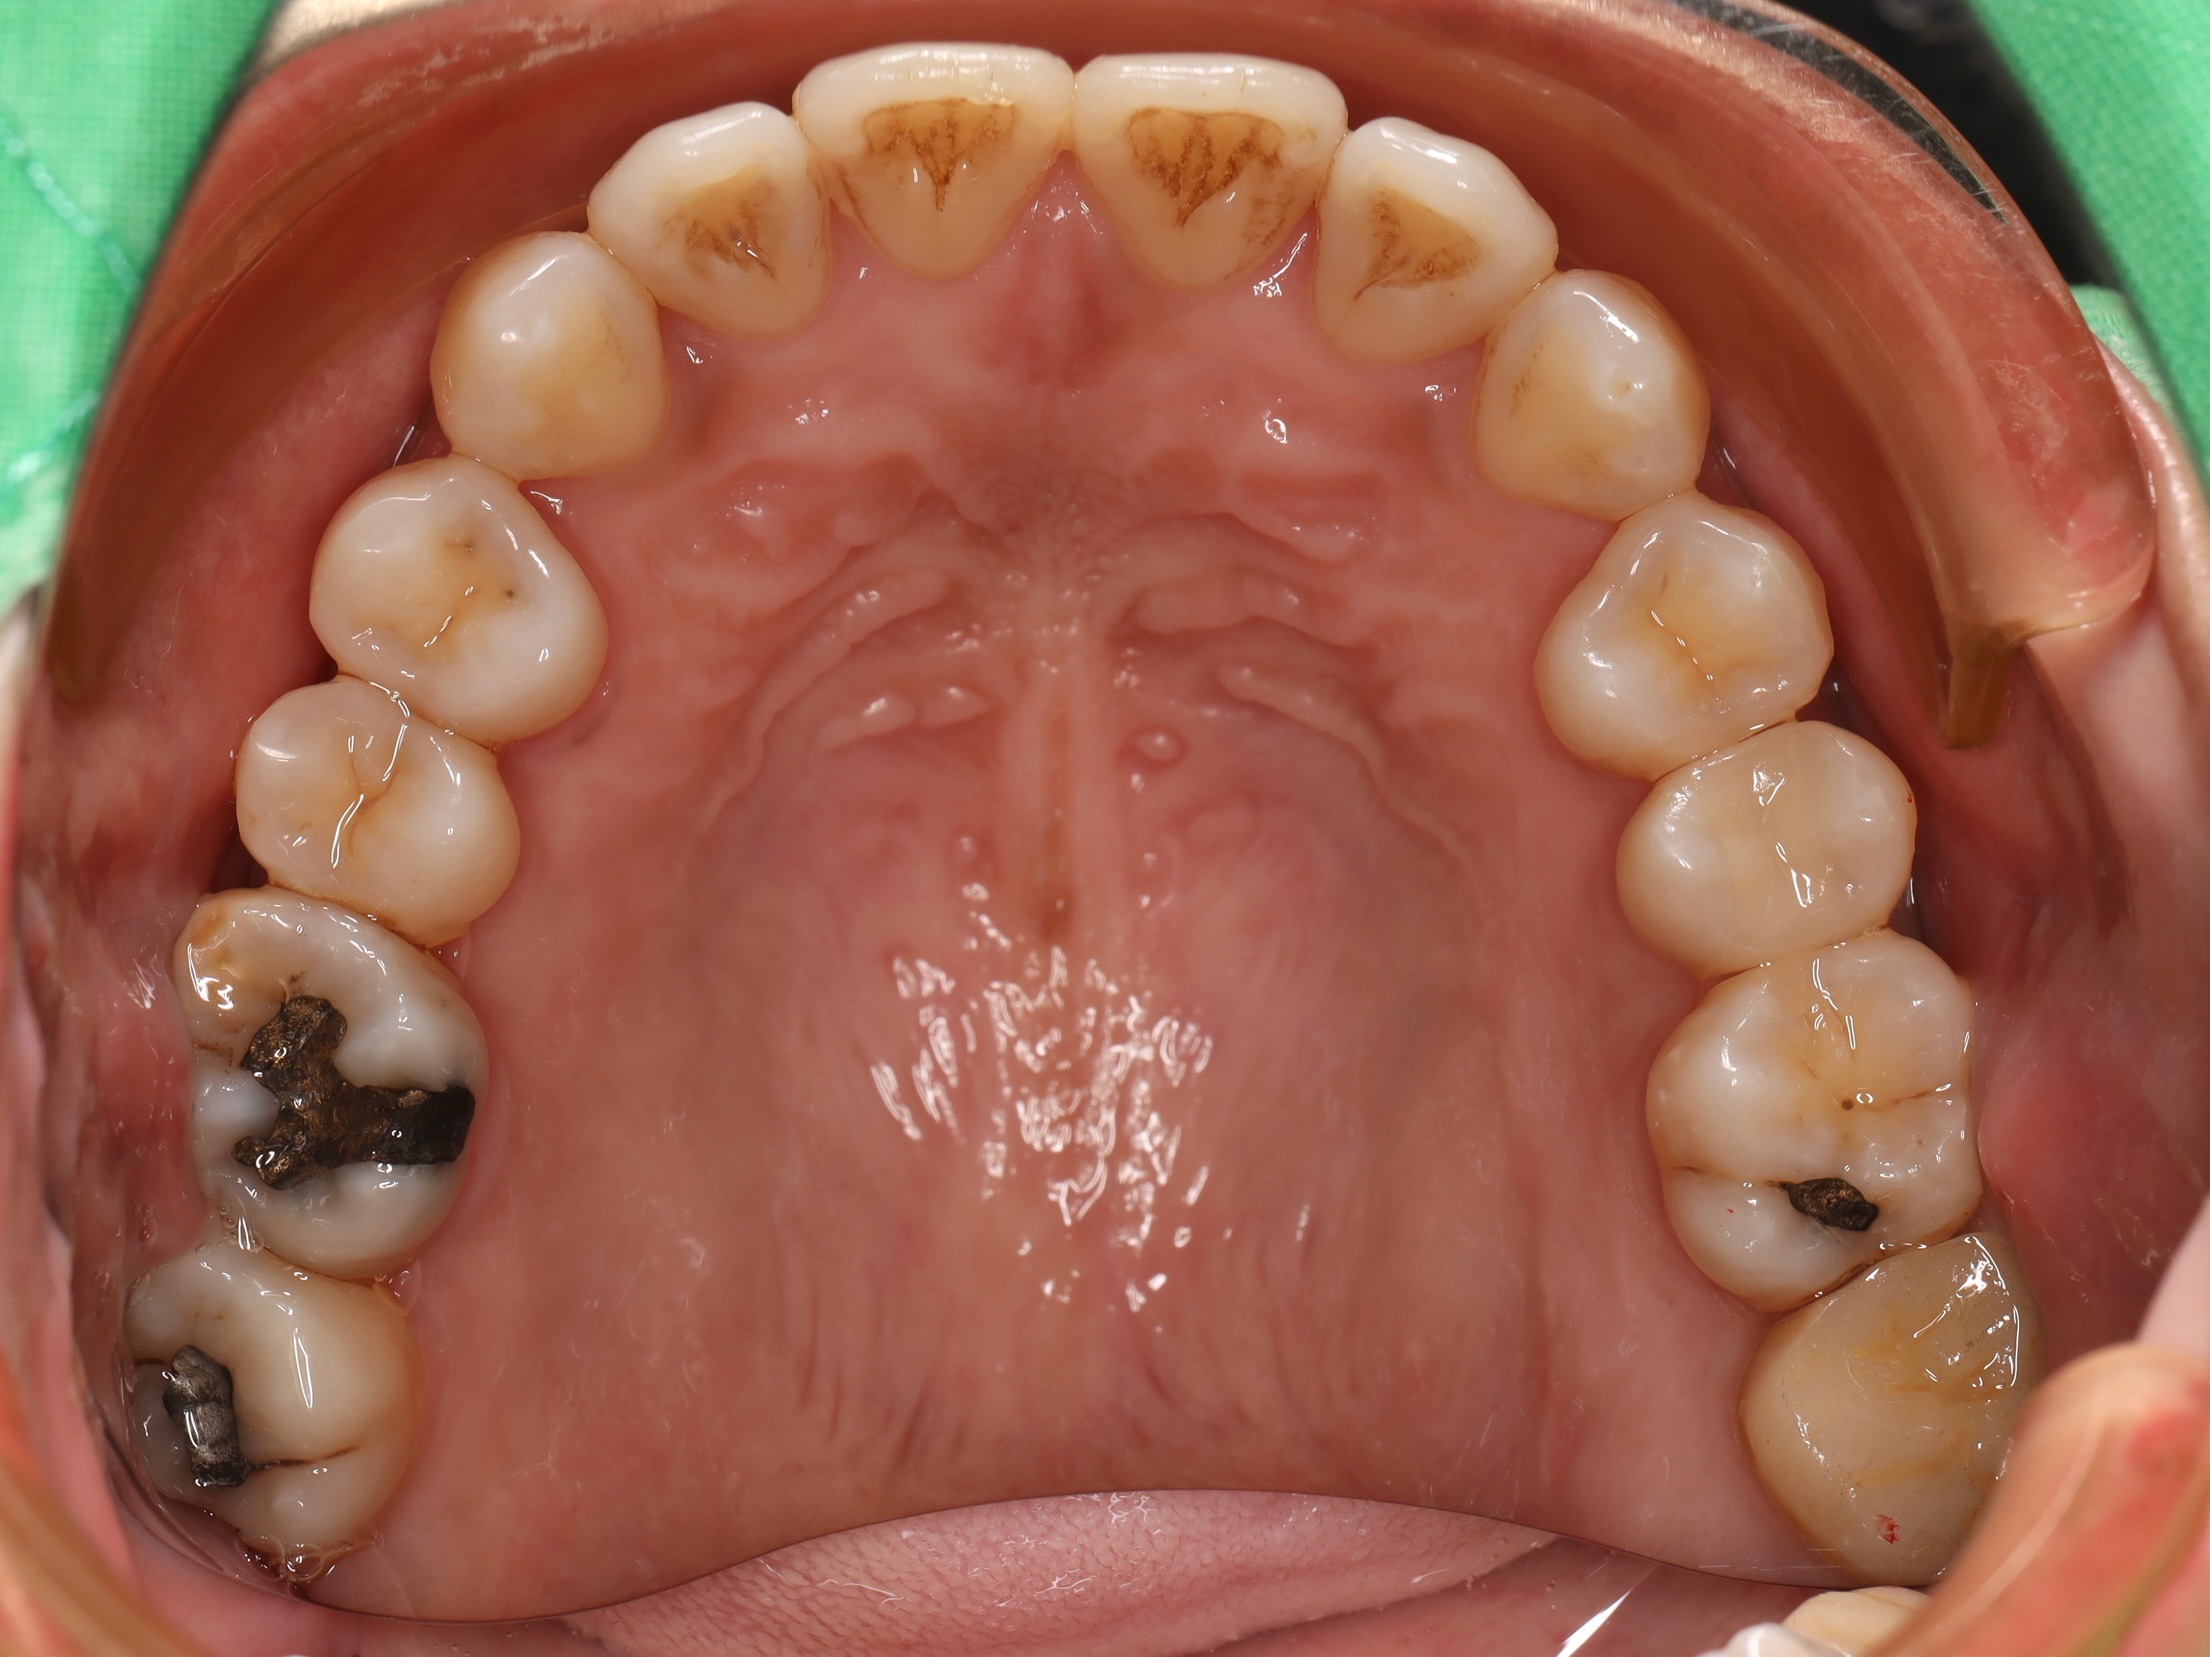

經過全口檢查與評估後,我們發現古小姐的口腔問題相當複雜,主要可以歸納為以下幾個項目:

全口牙周病問題 - 導致刷牙時流血的主因

右下牙套內部發炎 - 牙根處有感染狀況,需重新根管治療

左邊缺牙問題 - 長期缺牙導致排列與咬合問題

咬合與牙縫問題 - 影響整體美觀與功能

拆除右下方的舊牙套,進行二次根管治療,清除內部感染組織,並重新裝上全瓷冠,恢復功能與美觀。